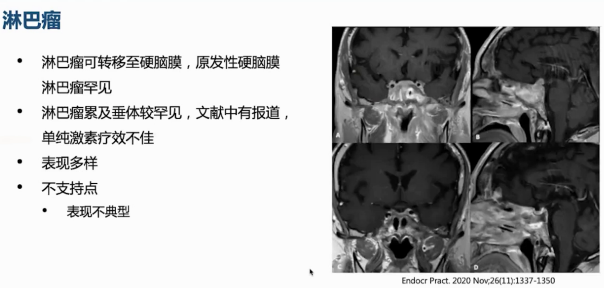

近2年前出现头痛,1年前出现多尿、多饮。外院垂体MRI提示鞍区占位,去氨加压素可控制尿量。病程中曾多次接受激素冲击治疗,治疗后鞍区病变缩小、症状缓解,但激素减量期间头痛反复,鞍区病变再次增大。

初始治疗采用足量激素加免疫抑制剂,激素逐渐减量。在三年随访过程中,激素量由50 mg qd逐渐减量至2.5 mg qd,免疫抑制剂也进行了调整。期间患者垂体病变相对稳定甚至有所减小,硬脑膜病变稳定,纵隔占位经心脏MRI随访大小无明显增长。